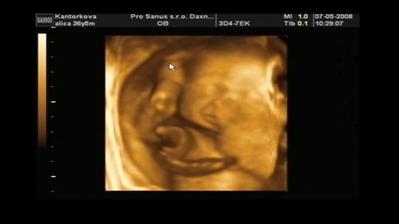

Naše druhé bábätko Filipko

V máji sme sa dozvedeli, že budeme mať druhého chlapčeka Samka alebo Filipka - stále sa nevieme rozhodnúť 🙂. Už sa ťa nevieme dočkať pokladík 🙂)

Náš druhý bubáčik sa narodil 8.septembra 2008 o 17:15 s mierami 50 cm a 3230 gramov